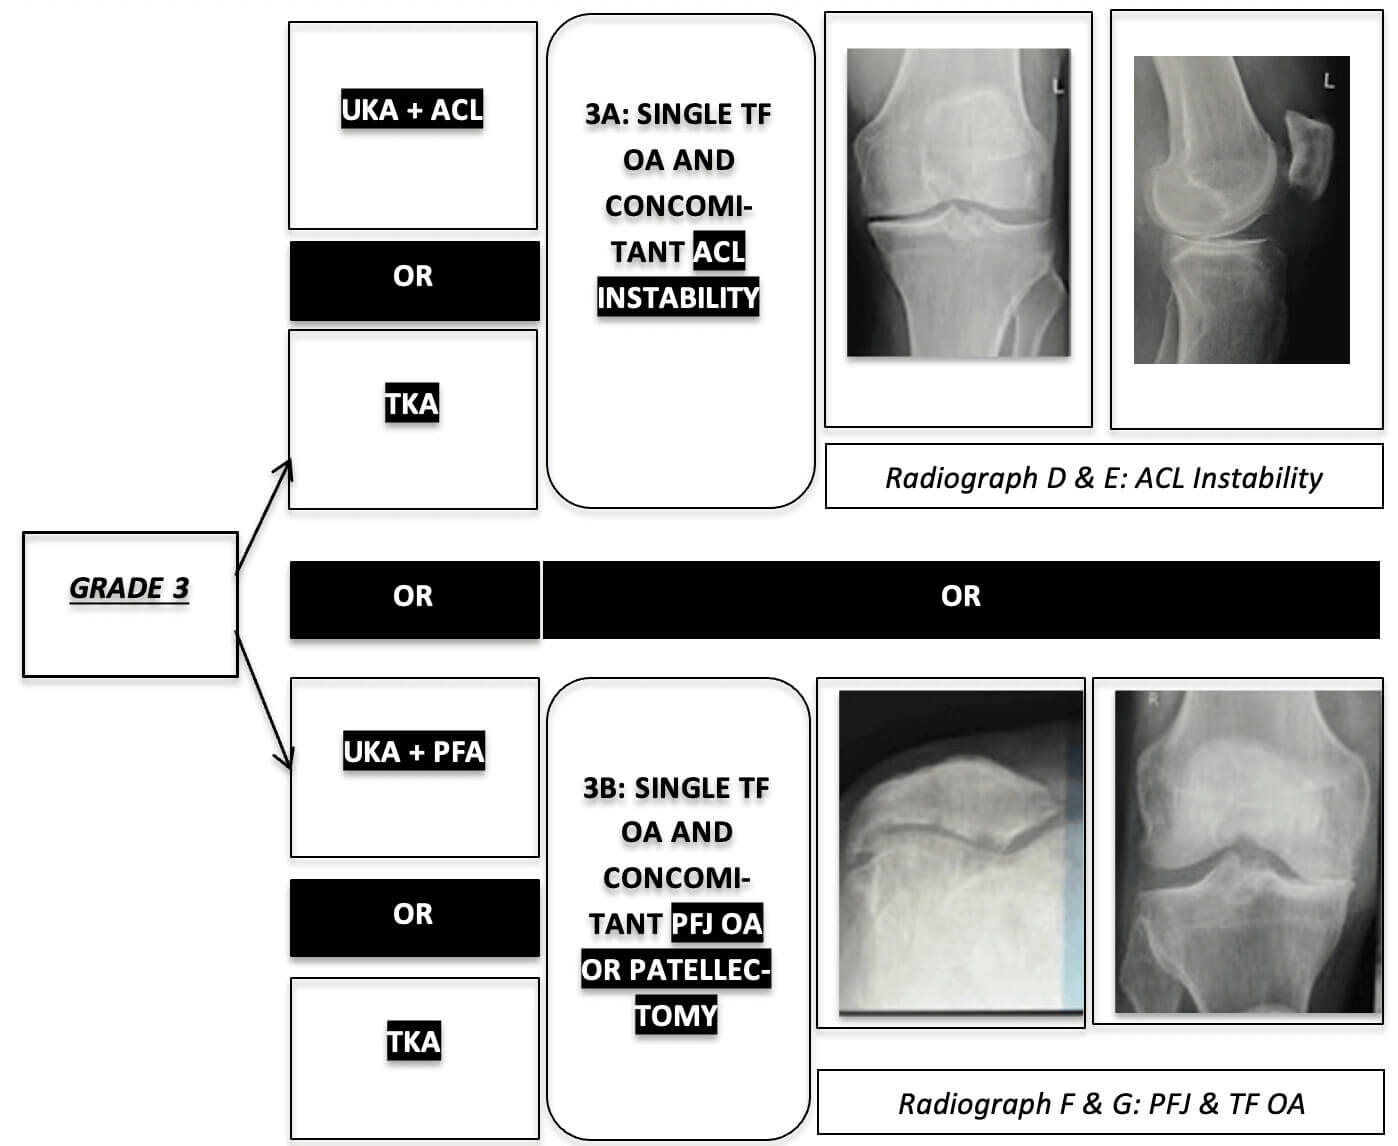

Knee Osteoarthritis Grading System.

KOGS FLOWCAHART

Footnote: Osteophytes are not a Contra-Indication. Confirm Contra-Lateral TF Space is > 5mm. Stress Reduction of Subluxation. No "Wedge Sign" (JLCA Less than 2 Degrees)